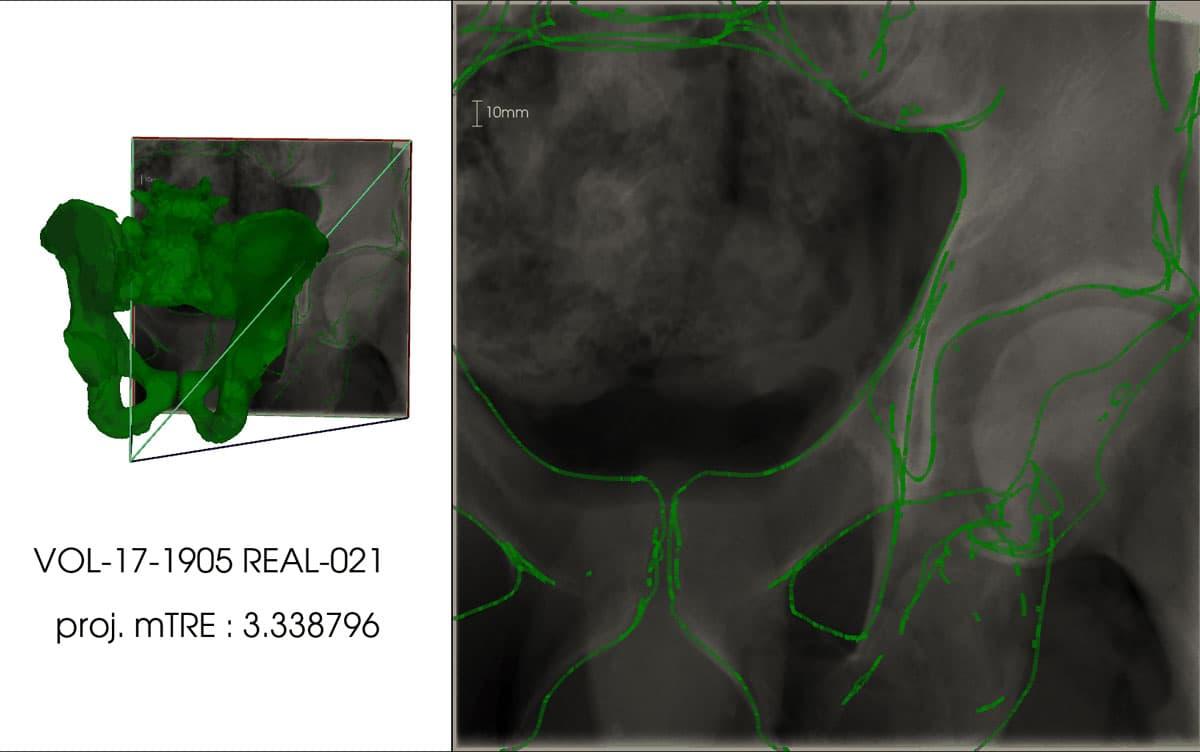

X-ray fluoroscopic images are commonly employed in orthopedic surgery. However, surgeons often struggle to accurately perceive the three-dimensional (3D) shape of the target area when working with two-dimensional (2D) X-ray images. Addressing this challenge, a team of researchers from the University of Tsukuba has developed a technology capable of automatically and precisely overlaying 3D computed tomography (CT) data onto intraoperative X-ray fluoroscopic images.

Tsukuba, Japan—The X-ray fluoroscopy machine is a medical device frequently used in orthopedic surgery. Despite its imaging capabilities, physicians heavily rely on their experience and knowledge to align the 3D shape of the target area using the 2D X-ray image. If X-ray images captured during surgery could be superimposed onto a pre-surgical 3D model (CT model) obtained from a CT scan, it would alleviate the cognitive load associated with visualizing the 3D shape from the 2D image, enabling surgeons to focus more on the surgical procedure. To achieve this goal, the superimposition of the X-ray image and CT model data should "work seamlessly, even when focusing on a specific body part (local image)," and the process should to be "fully automated." In this study, researchers met these criteria by employing a convolutional neural network capable of regressing the spatial coordinates of X-ray images. By incorporating correspondence formulation with deep learning techniques, they achieved highly accurate superimposition for local X-ray images.

The efficacy of this technique was verified using a dataset that included CT data and X-ray images of the pelvis. The superimposition of X-ray images and CT data yielded an error of 3.79 mm (with a standard deviation of 1.67 mm) for simulated X-ray images and 9.65 mm (with a standard deviation of 4.07 mm) for actual X-ray images. In the case of actual X-ray images, the superimposition of the X-ray image and CT data produced an error of 9.65 mm (with a standard deviation of 4.07 mm).